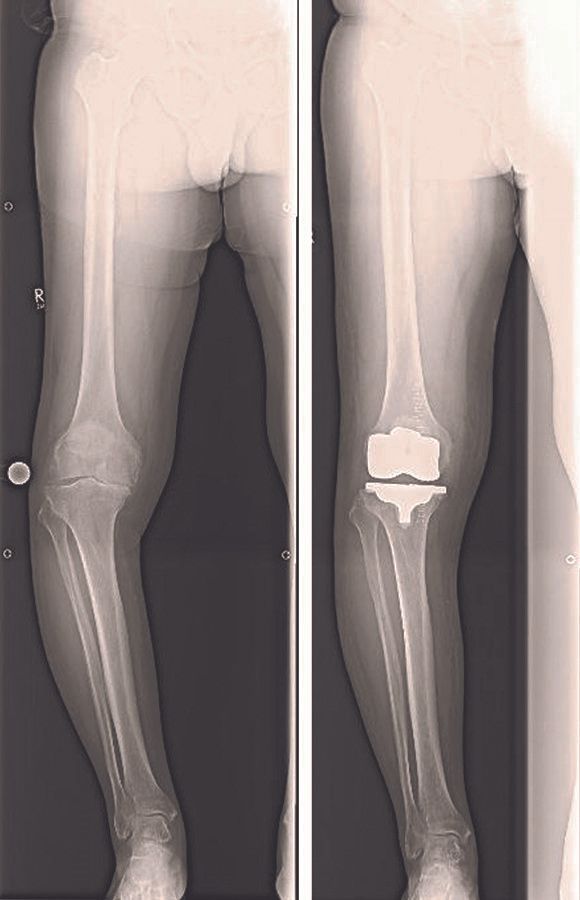

Considering these definitions, overall alignment can be described in two ways, using either the anatomical femoral-tibial (AFT) angle or the mechanical femoral-tibial (MFT) angle. The AFT angle is simply the angle between the anatomical axis of the distal femur and the anatomical axis of the proximal tibia. In a normal knee the AFT should be about 6° of valgus (range 4 to 9°). The MFT represents the angle between the mechanical axis of the femur (centre femoral head and centre distal femur) and mechanical axis of the tibia (centre proximal tibia and centre ankle). In a normal knee the MFT should be neutral 0° (range 3° valgus to 3° varus). While the AFT angle can be estimated from standard (short-leg) radiographs, measurement of the MFT angle requires long-leg radiographs (Figure 3). The AFT does not represent the real lower limb alignment and allows pure guessing of the mechanical axis of the lower limb.